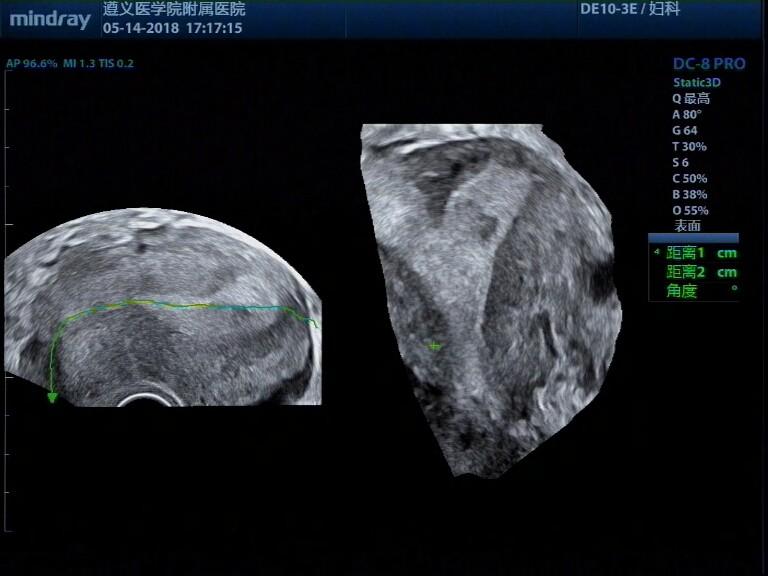

病例,31岁女性,纵膈子宫、畸胎瘤、子宫肌瘤

病例,31岁女性,纵膈子宫、畸胎瘤、子宫肌瘤。

病例来源遵义医学院附属医院